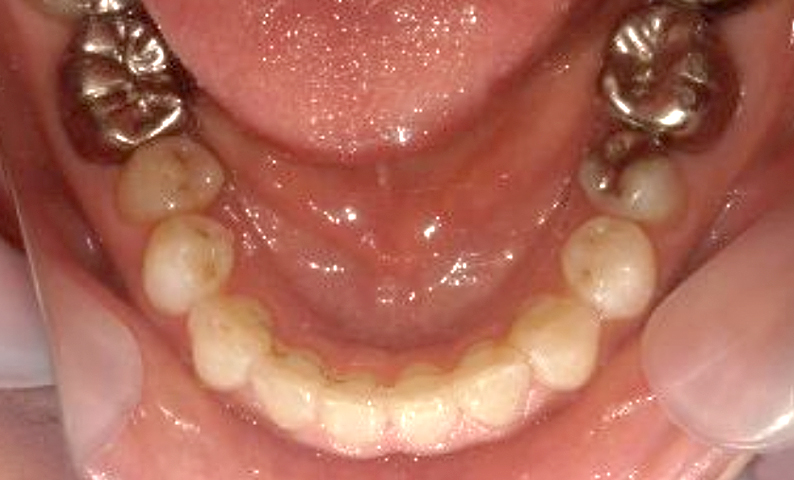

症例_030 上下顎の部分矯正

治療期間:12ヶ月金額:54万円+税女性八の字/V字型捻転歯前歯のガタガタ

| Before | After |

|---|---|

|